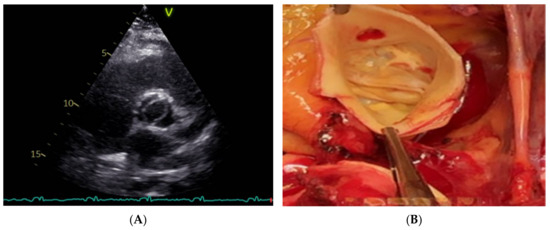

To describe patterns in BAV classification, a short-axis 2D scan is the best US view because it allows for detecting all the aortic orifices and characterizing cusps fusion and position. It is helpful to determine the presence of raphe and the calcification of the structures related to the components of the aortic valve. Furthermore, TTE, combined with a TC scan, supports determining the relations between cusps, or the angle of commissures, which is important for surgical methods and the width of the sinuses (Figure 7).

Figure 7.

(A) TTE. Right non-coronary cusps fusion. (B) In the picture from operation theater, it is possible to appreciate the fusion between the right cusp and the non-coronary cusp. Three sinuses are still viewed. Commissural geometrical juxtaposition forms a 180-degree angle.